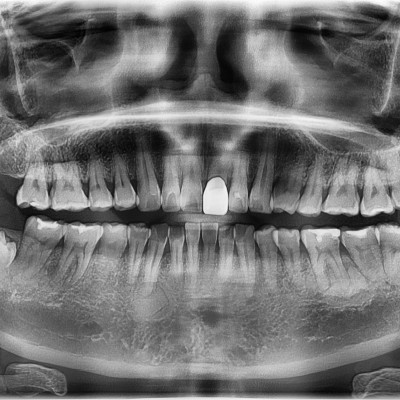

#18,48 사랑니 발치 #18,48 사랑니 발치 구강 외과 전문의가 당일 발치했습니다. ------------------------..

작성자 이턱이 작성일 03-11 조회 21